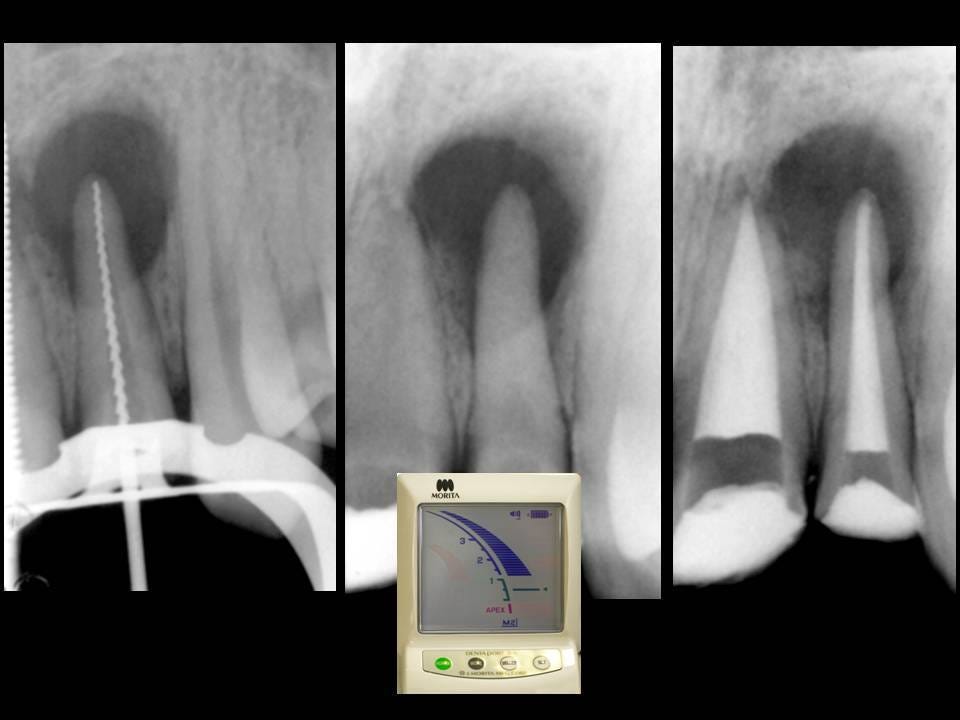

working length estimation in endodontic Apical Limit And Working Length In Endodontics in this paper, we review the different schools of thought for working length determination, and how apex locators work and how they. establishing the working length is an important step in endodontic treatment as inaccurate length determination may lead. in this paper, we review the different schools of thought for working length determination, and how apex locators. Apical Limit And Working Length In Endodontics.

(PDF) Radiographic assessment of endodontic working length Apical Limit And Working Length In Endodontics — this paper reviews the different schools of thought for working length determination, and how apex locators. — in this paper, we review the different schools of thought for working length determination, and how. — establishing the working length is an important step in endodontic treatment as inaccurate length determination may. establishing the working length is. Apical Limit And Working Length In Endodontics.

19 Determination of Working Length Pocket Dentistry Apical Limit And Working Length In Endodontics — thus, the predictable endodontic success demands an accurate working length determination of the root canal. — this paper reviews the different schools of thought for working length determination, and how apex locators. establishing the working length is an important step in endodontic treatment as inaccurate length determination may lead. in this paper, we review the. Apical Limit And Working Length In Endodontics.